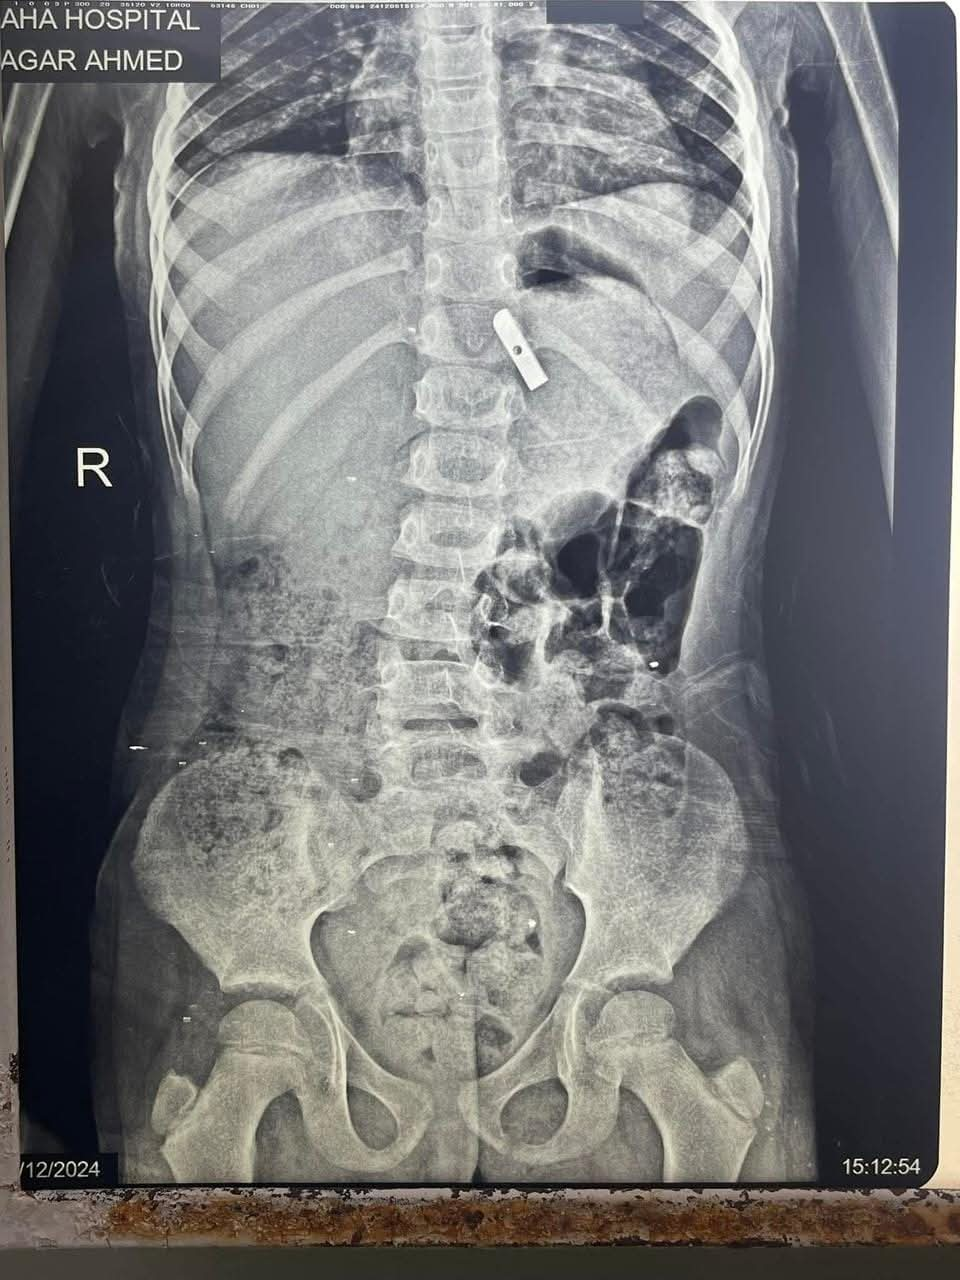

نجح فريق جراحي بمستشفى الأطفال التخصصي ببنها بمحافظة القليوبية، في إنقاذ حياة طفلة تبلغ من العمر 7 سنوات، تعاني ألم شديد بالمعدة وترجيع متكرر، حيث تبين ابتلاعها قطعة حادة من براية قلم رصاص، وتم استخراجها من المعدة.

وتابعت مستشفى الأطفال التخصصي ببنها، أنه تم حجز الحالة بالمستشفى وتم عمل اللازم من إشاعات وتحاليل، وتم تشخيص الحالة بوجود جسم غريب داخل المعدة، وعلى الفور تم دخول الطفلة إلى غرفه العمليات، وتم استخراج قطعة معدنية حادة من براية القلم الرصاص، من جدار المعدة باستخدام منظار الجهاز الهضمى.